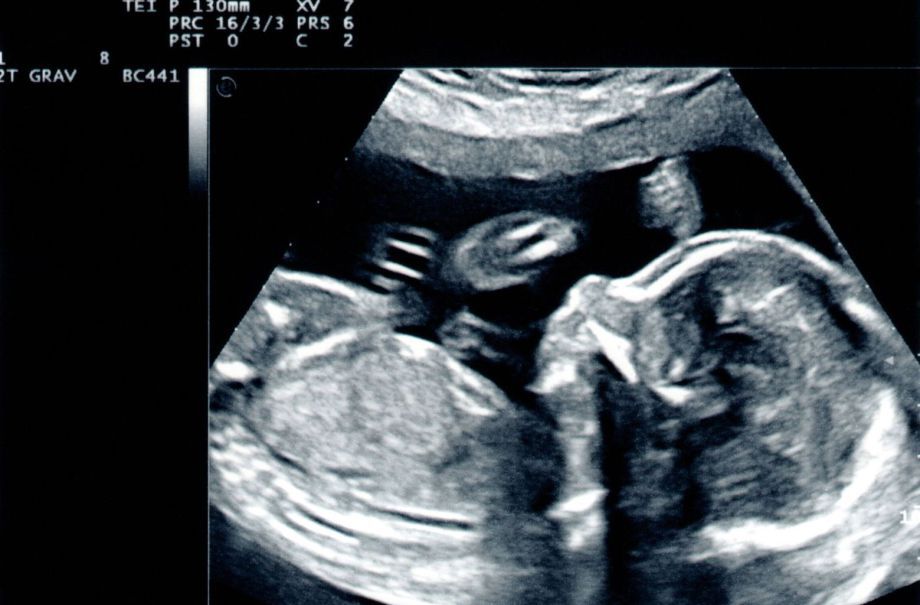

- Detailed Anomaly Check

- Wellbeing assessment includes position of baby and placental position.

- Growth report includes estimated weight of baby at current gestation.

- Amniotic Fluid check.

- Complimentary gender confirmed if requested

- 4D preview.